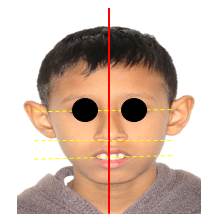

Paciente masculino de 10 años de edad, peso 23 Kg., estatura 123 cm., procedente de Jamundí, Valle del Cauca- Colombia. Asiste a consulta, en compañía de su tía, responsable del menor, quien refiere como motivo de consulta: “Mi sobrino tiene un solo diente adelante”. Al interrogatorio refiere: El niño es el segundo hijo de tres embarazos llevados a término; Antecedentes familiares, tía paterna padece diabetes, hipertensión y cáncer sin especificar. Antecedentes personales no reporta; la tía refiere que el niño, en la dentición decidua también presentó un solo incisivo central superior. Además, relata que sus otros dos hermanos presentan el mismo problema. Al examen extraoral se observa que la línea media no coincide con la punta de la nariz, ni con el centro del mentón; no presenta filtrum labial, el plano bipupilar no es paralelo a la línea comisural; existe incompetencia labial; orejas de tamaño, proyección e implantación aumentadas. (Figura 1) En el examen intraoral se observa un incisivo central único sobre la línea media del maxilar, ausencia de frenillo labial y papila incisiva, paladar oval y maloclusión clase II con proinclinación de incisivo central. (Figura 2 a, b y c).

Figura 1: Fotografía extraoral del paciente de frente donde se observa alteraciones a nivel de línea media y asimetría facial